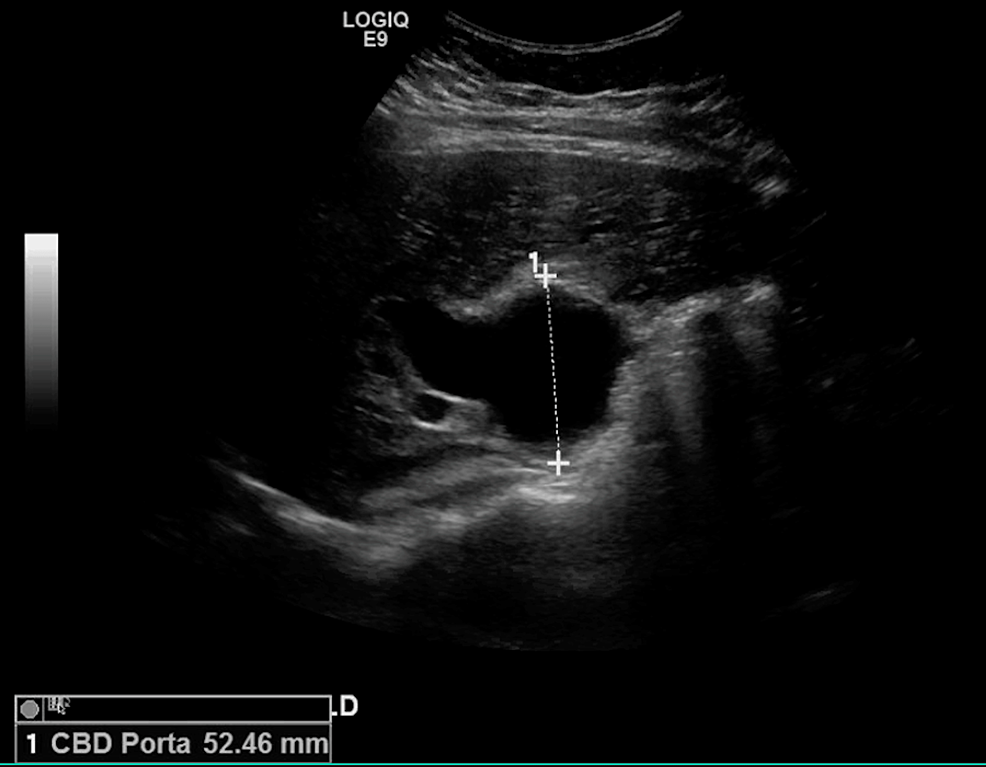

Cholestasis Atlas of Ultrasound Cholestasis Cholecystectomy intrahepatic cholestasis of pregnancy (icp) is a pregnancy liver. cholestasis is typically classified as intrahepatic or extrahepatic, depending on the location in which bile flow is impaired. It is also known as. intrahepatic cholestasis of pregnancy (icp) is a liver disorder in the late second and early third trimester of pregnancy. intrahepatic cholestasis of pregnancy (icp). Cholestasis Cholecystectomy.